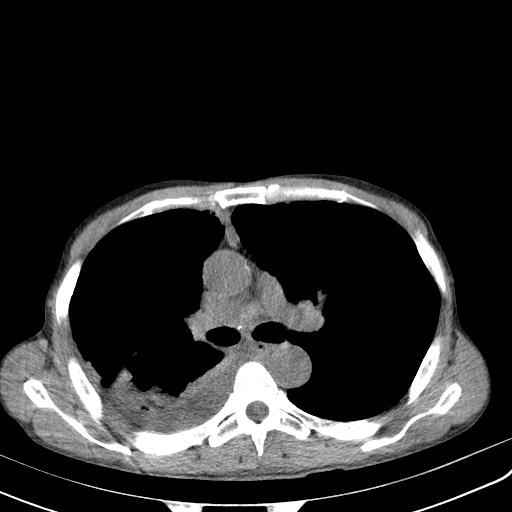

男性 75  咳嗽 一周前发热最高达39

右肺继发型tb并右侧tb性胸腔炎,右侧胸腔大量积液并右下肺膨胀不全,慢支肺气肿、多发肺大泡。建议抽胸水实验室检查并复查排除恶性在占位。

右上肺继发型肺结核,右胸腔中等量积液。

结核的基础上有纵隔淋巴结肿大,右侧有胸水,但右侧纵隔反而窄,说明有肺有不张。

再就是右下肺有块影,和不张混合,还是不能除外肺癌。

补充材料,患者2月份ct片大致正常,双侧胸腔积液,2月份抽胸水未发现ca细胞,现患者发热,痰多,各气管通畅,

1)右肺继发型肺结核。2)左肺胸膜下多发性肺大泡。3)右侧胸腔积液。